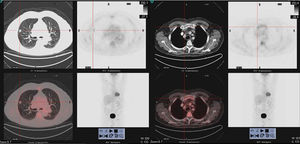

Imágenes de 18F-FDG PET/TC que muestran (a la izquierda) un nódulo sólido hipermetabólico (SUVmáx 7,5), espiculado, que presenta contacto puntiforme con pleura y con la cisura, de unos 14mm, situado en el LSD en el segmento anterior. Lesión ósea hipermetabólica (a la derecha), con componente lítico en el extremo distal de la clavícula derecha (SUVmáx 8,4).

Se presenta el caso de un paciente de 77 años, exfumador con un índice acumulado de 50 paquetes/año, con antecedentes de dislipemia, gammapatía monoclonal de significado incierto (GMSI) IgG lambda (componente monoclonal [CM]: 4,8g/l) diagnosticado en 2014, estable y sin evidencia de progresión, controlado anualmente por hematología, y EPOC moderada no agudizador frecuente, en tratamiento broncodilatador, con grado de disnea mMRC 1, y sin ingresos previos por exacerbación. Asintomático desde el punto de vista respiratorio, y sin cuadro constitucional acompañante, en noviembre de 2017, tras los hallazgos en la radiografía de tórax de un nódulo pulmonar en un control rutinario se realizó una tomografía axial computarizada (TAC) de tórax que evidenció un nódulo espiculado de 13mm en segmento anterior de lóbulo superior derecho (fig. 1), con contacto pleural y retracción de la cisura menor adyacente. La analítica (bioquímica, incluyendo proteínas totales, dosificación de inmunoglobulinas, proteinograma e índice de cadenas ligeras libres, hemograma y coagulación) fue normal. Se realizó una tomografía por emisión de positrones (18F-FDG-PET/TC) que mostró un nódulo sólido hipermetabólico (SUVmáx 7,5) espiculado de 14mm con contacto puntiforme con pleura y cisura, sugestivo de etiología neoplásica primaria (fig. 1) y múltiples lesiones óseas hipermetabólicas, de componente lítico en el extremo distal de la clavícula derecha (SUVmáx 8,4) (fig. 1) y en el cuerpo vertebral de D3 y de aspecto blástico en la unión cabeza/cuello femoral izquierdo (SUVmáx 12). Estas lesiones fueron atribuidas inicialmente a etiología metastásica. Además, se describía una irregular distribución del trazador en otras estructuras óseas, no concordante con lesiones morfológicas y con discreta actividad metabólica en manubrio esternal, que no permitían descartar una etiología secundaria. Se procedió a hacer una biopsia transtorácica guiada por TAC de la lesión pulmonar que fue positiva para adenocarcinoma de origen pulmonar. Con la intención de completar la estadificación (T1bN0Mx) se decidió hacer una biopsia de la lesión lítica de la clavícula derecha que fue positiva para neoplasia de células plasmáticas, compatible con plasmocitoma/mieloma múltiple (MM).